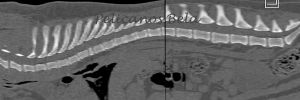

PELICANOS BELA

| Name | PELICANOS BELA |

| Sex | Male |

| Birthday | 28.03.2017 |

| Color | Brindle |